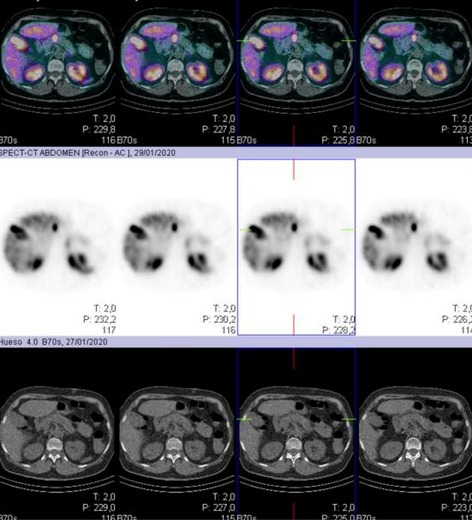

Aims: Stereotactic navigation is a computer-assisted surgical system that enables surgeons to track surgical instruments in conjunction with CT/MRI during surgery. It is well established in neurosurgery and orthopedic surgery. Stereotactic navigation in the gasytrointestinal tract remains challenging because of tissue deformation and or organ motion. The aim is to evaluate the first results of the feasibility and precision of stereotaxic navigation in laparoscopic surgery for colic cancer. METHODS: Patients with colorectal cancer undergoing minimally-invasive approach were enrolled. Patients were divided in two groups: patients with preoperative CT-Scan performed with fiducials at our institution not needing intraoperative images acquisition(Arm1) and patients with CT-scan previously performed needing intraoperative acquisition (robotic c-Arm) of images to establish intraoperative navigation(Arm2). The "accuracy" of surgical navigation is defined as the distance measured between the position of "surgical" previously defined anatomical landmarks, pointed with a surgical instrument tracked by the navigation system, and corresponding location of the instrument in the navigation image. A distance equal to or less than 4 mm between the two locations is considered as an optimum accuracy.

Results: Navigation was performed in 6 patients (3males/3females), mean age 70 yo (54–85). Procedures performed: 4 right, 1 total, 1 sigmoid colectomy. Four patients in ARM1; 2 patients in Arm2. C-Arm acquisition time in Arm2 were 23 and 10 min. Mean registration time was 2.8 min (1–5). Mean navigation time was 22.5 min(18–26). Measures of navigation before dissection showed a mean difference of 57.1 mm(15–159.2); after dissection mean distance was 12.7 mm (3.8–19.5). Navigation improved identification of landmarks. Main difficulties encountered during navigation were: CT-Scan and C-Arm images fusion; change of landmarks not visible on CT-scan, difficult instrument tracker fixation to laparoscopic grasper because not conceived for that, patient tracker not visible, structures identified for navigation sometimes altered after dissection or hidden before mobilisation, difficulty to align in a perpendicular line the instrument plate with the camera site, one navigation not done because instrument tracker not recognized.